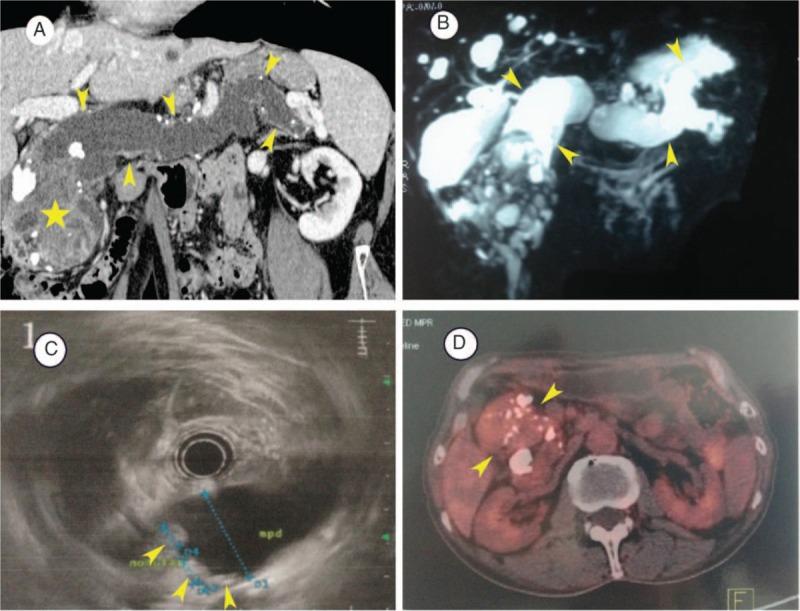

Pancreatic carcinosarcoma mimics malignant intraductal papillary mucinous neoplasm: A rare case report and literature review.

Carcinosarcoma, an extremely rare pancreatic primary tumor, is characterized by coexistence of both carcinomatous and sarcomatous components. Due to its rarity, the clinical manifestation and imaging features have not been recognized. An accurate diagnostic method has not been available and a widely accepted guidelines instructing treatment has not been established.

PATIENT CONCERNS

We present an uncommon case of pancreatic carcinosarcoma (PCS) which has been preoperatively diagnosed as pancreatic malignant intraductal papillary mucinous neoplasm. A radical resection, including total pancreatectomy (TP) and splenectomy, was performed.

The diagnosis of PCS was confirmed by postoperative pathology.

A radical resection, including TP and splenectomy, was performed. The patient was followed up by abdominal contrast-enhanced computed tomography scan and blood tumor marker examination.